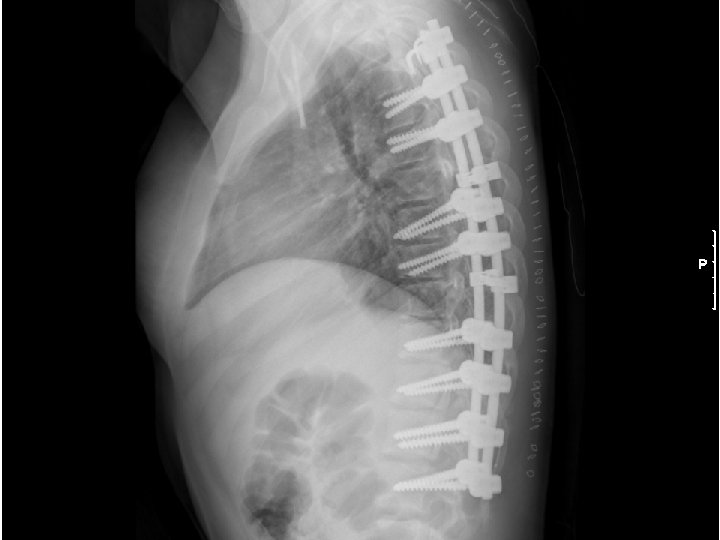

Surgical Treatment for Scoliosis • Curves in growing children greater than 40 º require a spinal fusion (Risser grade 0 to 1 in girls and Risser 2 or 3 in boys) • Skeletally mature patients can be observed until their curves reach 50 º • Posterior spinal fusion is best choice for thoracic curves • Anterior spinal fusion is best treatment for thoracolumbar and lumbar curves

Surgical Treatment for Scoliosis